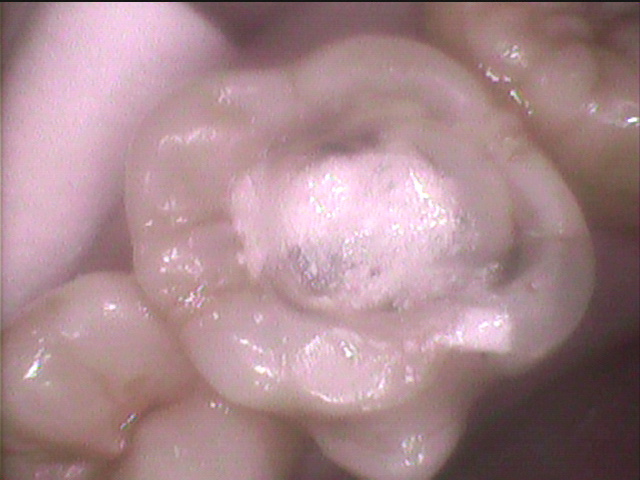

インレーが浮き上がっています。

インレーを除去するとインレーの下はレジン充填があった

さらに虫歯を追いかけて、薬剤充填をして様子を見ます。

虫歯菌を殺す抗生物質です。